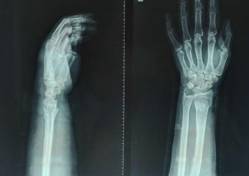

手法复位小夹板固定治疗骨折

优点:免于开刀之苦。

中医骨伤特色明显:包括特色复位手法、传统夹板传承并革新;中药经验方药内服、外敷及离子导入疗法、中药水浴、熏蒸以及骨折后康复治疗等等可有效促进骨折愈合、治疗骨不连;吊兜悬吊牵引结合功能锻炼保守胸腰椎压缩性骨折;骨髓炎广泛开窗换药+外固定支架技术、感染骨段切除骨延长技术治疗,结合中医药辩证治疗等。

微创治疗肱骨干骨折

优点:闭合复位,不干扰骨折断端,中心固定,利于愈合。